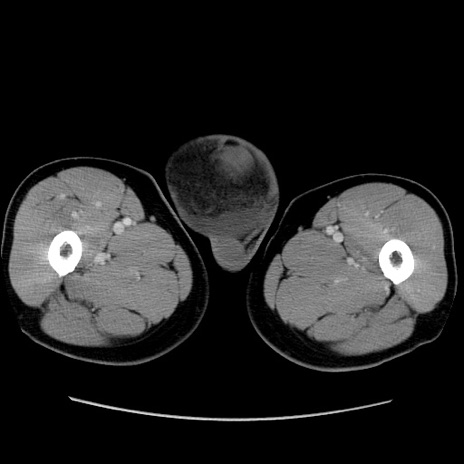

症例34(横断像)

【症例】60歳代 男性

【主訴】右鼠径部膨隆

【現病歴】1年程前より右鼠径部膨隆あり。自己にて還納可能だったため放置していた。3時間前より右鼠径部の脱出を認め、還納困難となり受診。

【既往歴】高血圧

【身体所見】右鼠径部に小児頭大の膨隆あり。弾性硬であり、用手還納は困難。左鼠径部にも膨隆を認める。脱出はなし。

【データ】WBC 15500、CRP 測定なし